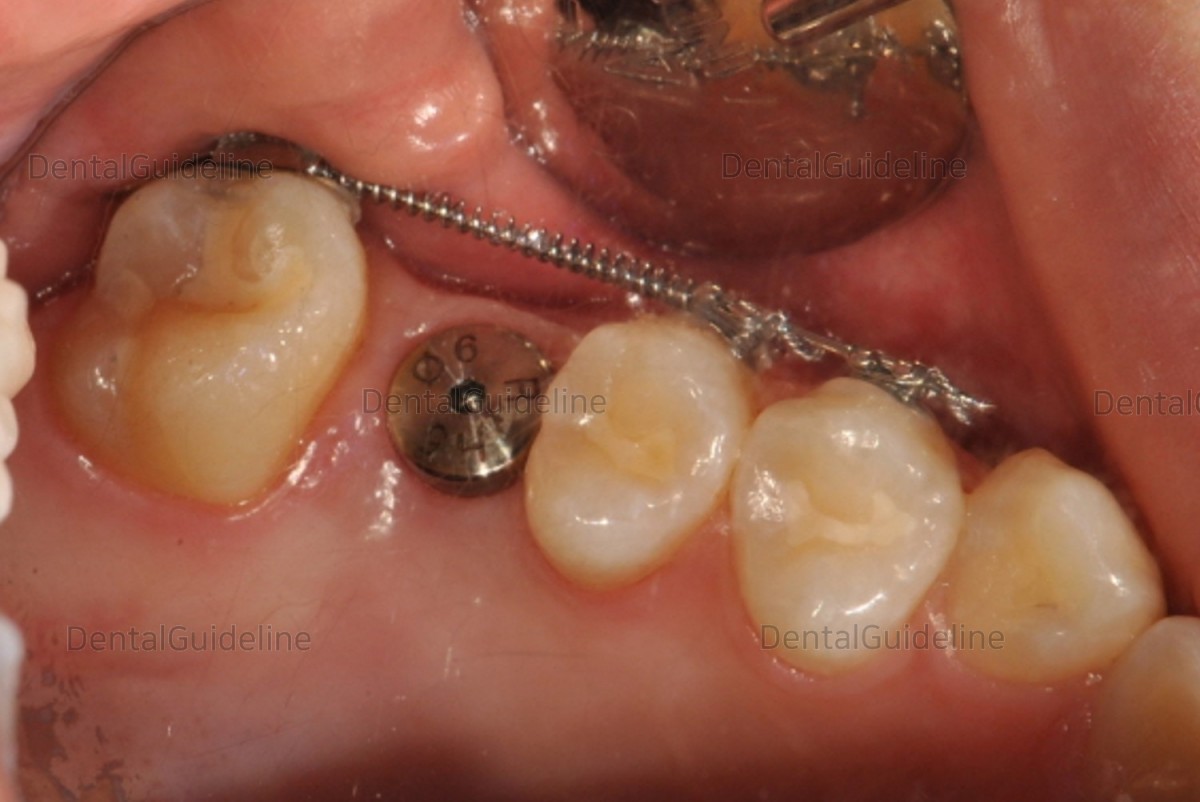

![]()

20. HA was connected by extending the gingiva from a small size

to an appropriate size.

21. Impression taking.

22. Custom abutment was connected.

23. Zirconium crown.